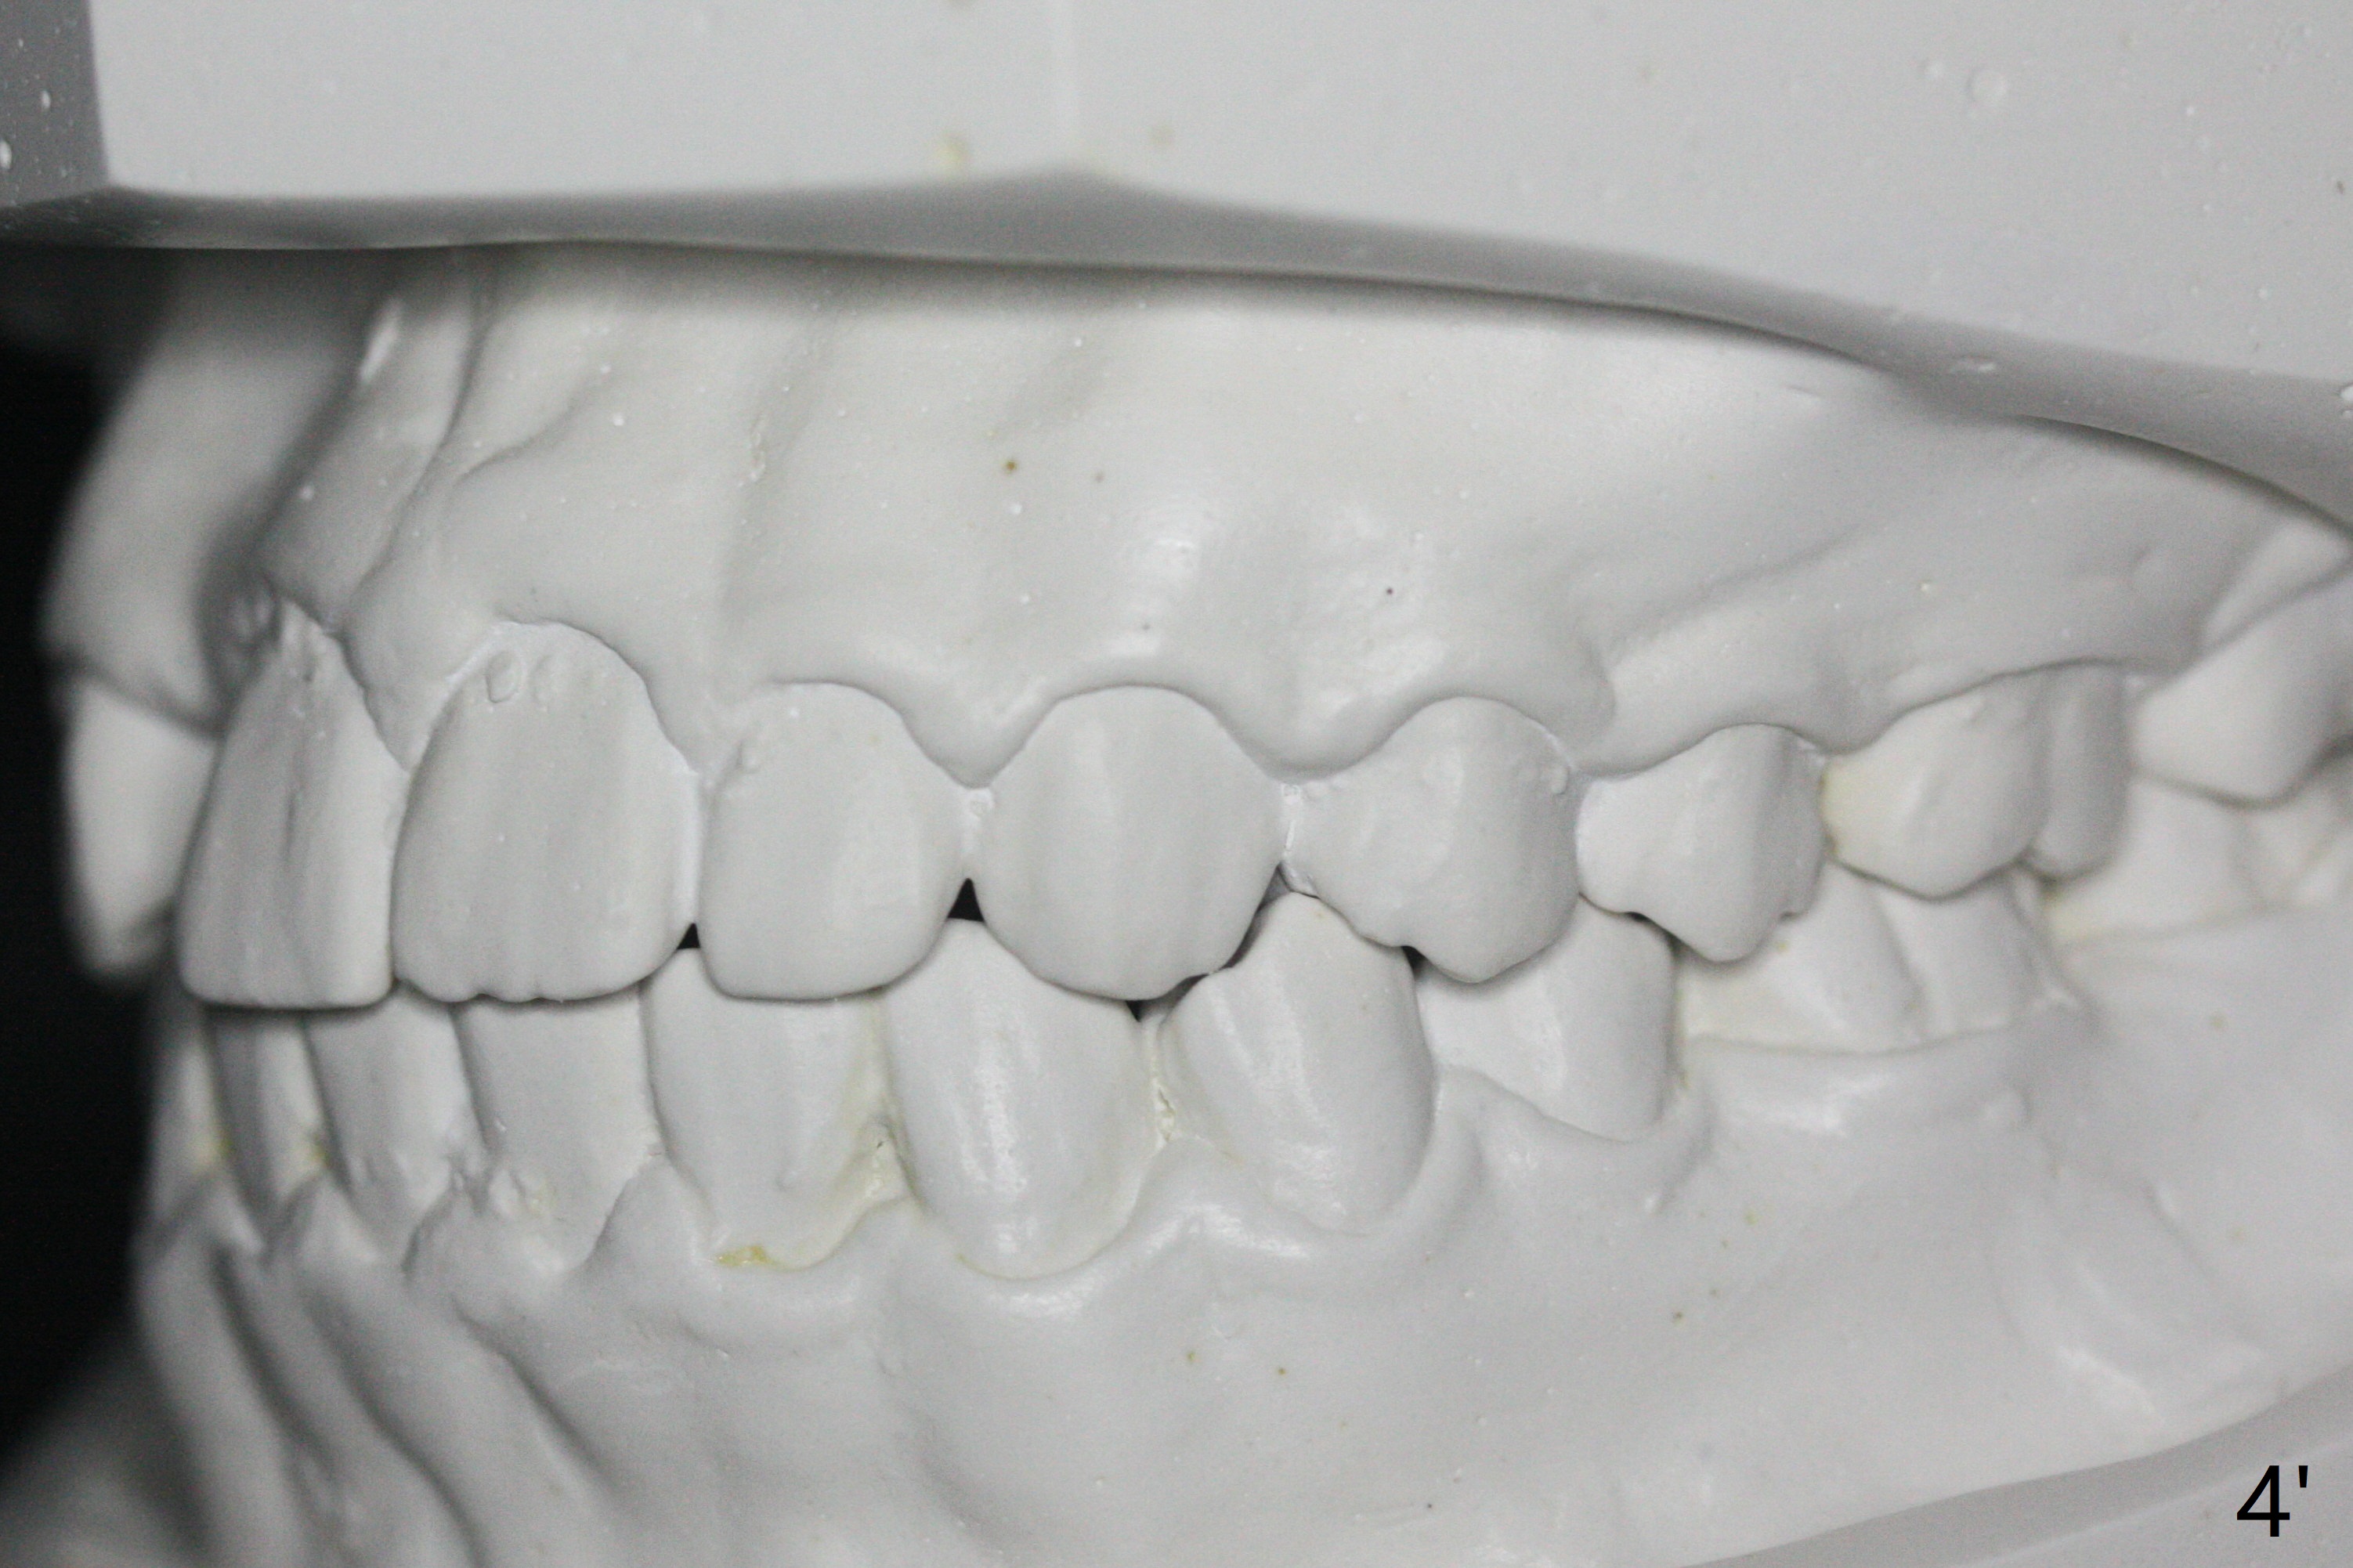

A 15-year-old man finishes orthodontic treatment for congenital missing lateral in 13 months. Molar Class I relationship remains the same (Fig.1,2,4,5). The upper diastemata mesial to 4s (Fig.4,7") close with correction of the upper midline deviation (Fig.2'-4'). The kid is unpleased with the elongated UR1 (Fig.2',3'). In fact it is a preexisting condition (Fig.2 arrow, 2"), but bracket placement at UR1 should have been overcorrected (incisal placement, Fig.3"). The intrusion should be done (Fig.4") before closure of the diastemata, since anchorage may be weakened when the separation between UR1 and 3 increases by using open coil spring. To prevent immediate relapse of the diastema between the upper central incisors, a fixed retainer is placed lingual before debracketing (Fig.6,6',6").